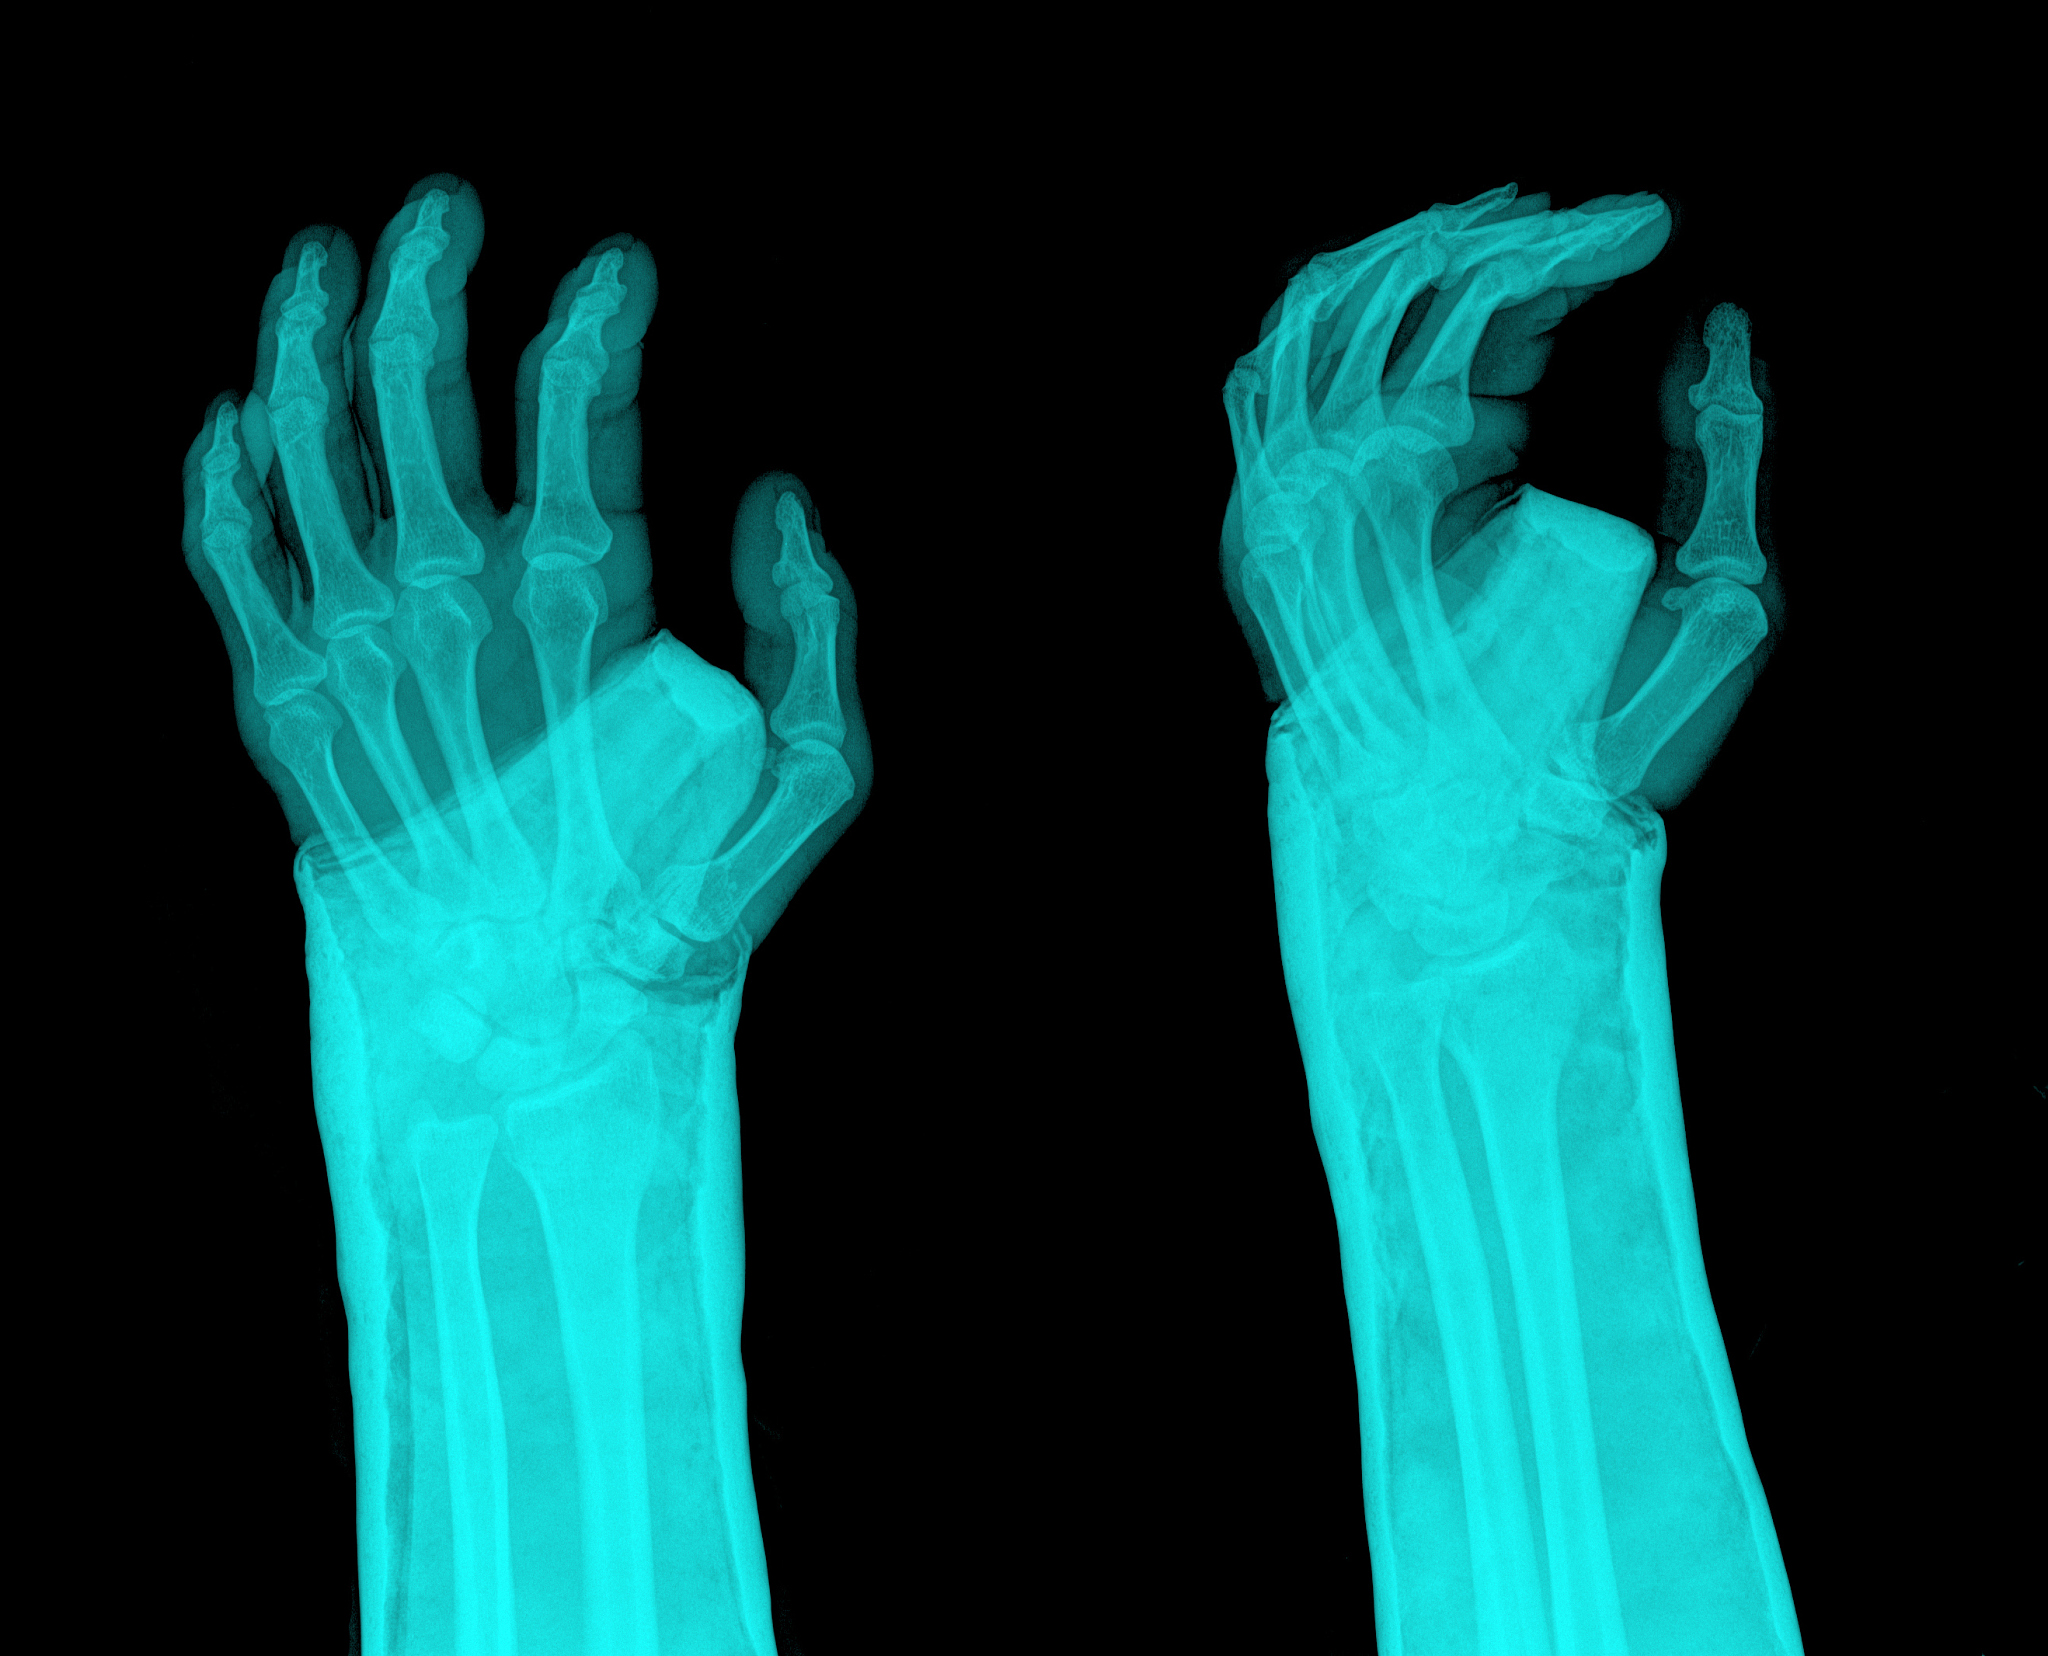

折腕控制的危害:关节结构的破坏

折腕控制破坏的是手腕部位的关节结构。当手腕被强烈地弯曲或扭转时,关节结构包括韧带、滑膜、半月板等可能会受到损伤。这种损伤可能导致关节的不稳定性、疼痛、肿胀等症状,严重的情况下甚至可能导致关节脱位或骨折。因此,在进行运动或活动时,特别是需要用到手腕力量的活动,应该避免过度折腕控制,以保护手腕的关节结构。